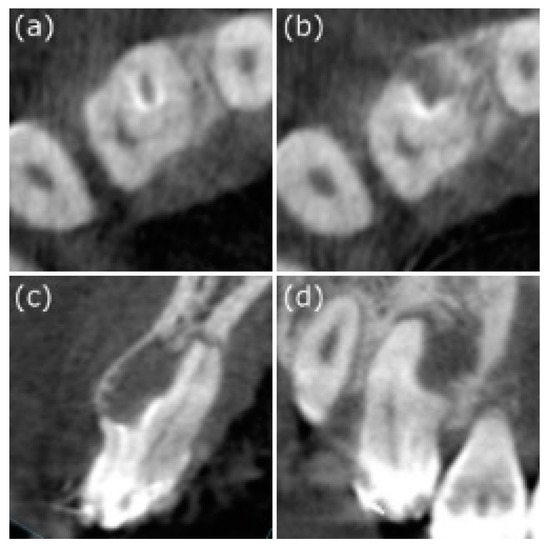

However, the orthodontist was concerned that the significant size of the lesion around the root might affect root movement during the orthodontic treatment. In addition, according to the literature, a metal orthodontic gear attached to the tooth surface might cause false-positive results in traditional electric pulp testing, thereby leading to an inaccurate evaluation of the pulp vitality. Therefore, laser Doppler blood flow monitor and imager (MoorLDI-2λ) was scheduled for further assessment.

In the flux image, red color indicates the area with sufficient supply of blood. In other words, the red parts stand for vital pulp. Therefore, it is suggested that the three front teeth are vital. According to the perfusion unit’s (PU) analysis of the laser Doppler, circle 1 refers to the red circle. Further, the statistics show that PU has no significant difference from the other two in the control group. It shows that the tooth is still vital and that regular follow-up could suffice (Figure 5). Since laser Doppler has successfully enhanced the diagnostic accuracy, unnecessary interventions can be avoided. At two years, the periapical area showed normal bone density (Figure 2d). Moreover, the tooth still responded normally to electric pulp testing. The PRICE 2020 flowchart showing the steps involved in the case report (Figure 6).

Figure 5.

Laser Doppler to track the pulp vitality. (a) In the flux image, the red color represents areas of abundant blood flow, corresponding to the video image (b), in which the red circle shows the tooth to be measured. According to (c), PU analysis of laser Doppler revealed that circle 1 was the red circle (* means the circle 1 was selected as the reference). The calculated perfusion units in the diseased tooth were not significantly different from those in the two control teeth, indicating that the tooth remained viable. Continuous follow-up was recommended.